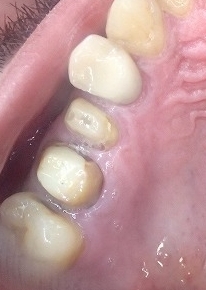

右上 歯冠破折 金属も白い歯に交換ご希望です。

歯根が折れている歯は、保存不可能ではありませんが

本来なら抜去するのが一般的治療法の歯ですが

根管治療と土台作りして保存処理します。

治療後のリスクはありますが

保存をご希望なさる方は、

なるべく保存してかぶせものを作り

保存しています。

ファイバーコアと金属の除去 治療のリスク 予後に関して

歯根が破折しているので、

一般的な歯科医院では、抜去すると思います。

歯肉を整形して根管治療しましたが

歯根が折れているのでファイバーコアを制作しても

制作後に下記のような問題が通常よりハイリスクとなります。

●ジルコニアクラウンがコアごと脱離するリスク

●破折した部分の歯肉から炎症を起こす

●トラブル時には抜去の可能性がある。

その際にはブリッジやインプラントを考えなくてはならない